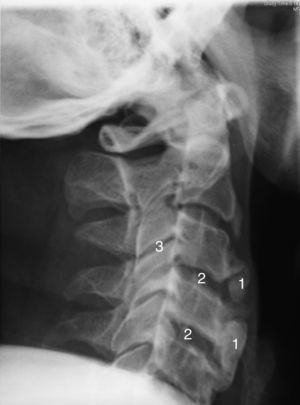

The assessment of the radiological changes in the cervical spine of this patient over a 5-year period revealed an increase in osteophyte size and in the ossification of anterior cervical ligament, which affected several contiguous vertebrae (Figs. 1 and 2). This could explain an extrinsic cause of the dysphagia. There are other radiological features of interest, such as the relative preservation of the intervertebral disc space and the absence of involvement of the facet joints.